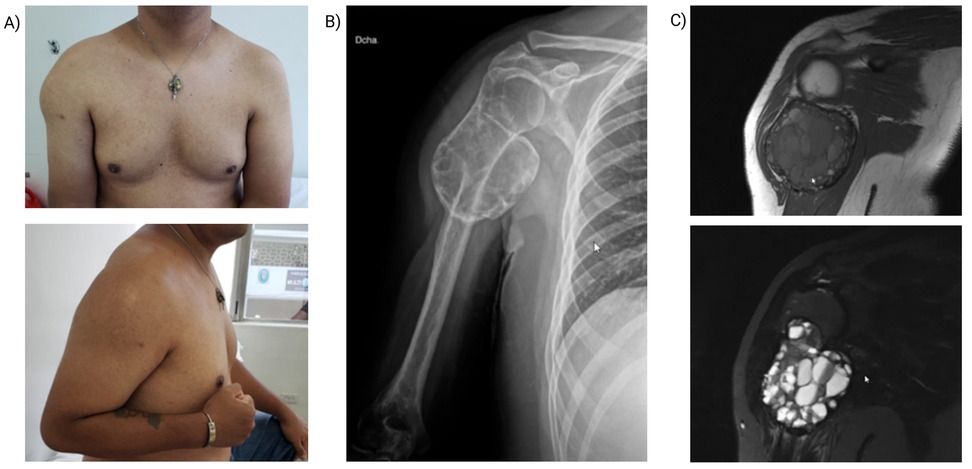

A 36-year-old man presented with an 8-month history of a progressively enlarging, tender mass in the right proximal humerus after an impact with a chlorine container. He had attempted traditional therapies, including consultation with a sobador (bonesetter), without improvement. Over the preceding month, he reported worsening pain, further enlargement of the mass, and marked functional decline. His medical history was notable for a penicillin allergy. On examination, there was localized edema and chronic tenderness with severely restricted active range of motion (ROM) of the right shoulder; flexion and abduction were each limited to 10°. Initial radiographs demonstrated an irregular cystic lesion of bone, prompting a provisional diagnosis of a neoplasm of uncertain behavior (Figure 1). Analgesics were initiated, and a core needle (Tru-Cut) biopsy was performed.

Figure 1

A) Two photographs showing a person's upper chest and arm, highlighting asymmetry and a visible lump on the shoulder. B) An X-ray of a shoulder displaying the bone structure, with an abnormal growth near the joint. C) Two MRI images showing a mass in the shoulder area, indicating a possible tumor or abnormal tissue growth.

Figure 1. Preoperative patient evaluation. (A) Clinical image showing soft tissue displacement at the right proximal humerus. (B) Anteroposterior radiograph reveals a bony lesion in the posterolateral metaphysis of the proximal humerus with a bulging periosteal reaction, internal septations, and a soap-bubble appearance, characteristic of aneurysmal bone cyst (ABC). (C) Coronal MRI: T1-weighted image (top) shows soft tissue displacement and inflammatory changes in the deltoid muscle. T2-weighted image (bottom) demonstrates fluid levels within the lesion, consistent with ABC.

3.2 Imaging

Imaging features vary by evolutionary stage. In our case, radiographs of the proximal humerus showed a lytic, expansile, eccentric lesion with internal trabeculations, cortical thinning, and a “soap-bubble” appearance—classic for ABC (Figure 1) (9, 10). Computed tomography (CT) demonstrated multiloculated cystic spaces with fluid–fluid levels, a hallmark produced by sedimentation of blood products. Magnetic resonance imaging (MRI) confirmed the cystic architecture with heterogeneous T1/T2 signals, enhancing septa, and absence of solid nodular components, effectively arguing against telangiectatic osteosarcoma (3). Although nonspecific, bone scintigraphy highlighted hypervascularity, supporting an active metabolic process (1). Altogether, these findings favored a primary ABC; the principal radiologic differential diagnoses are summarized in Table 1.